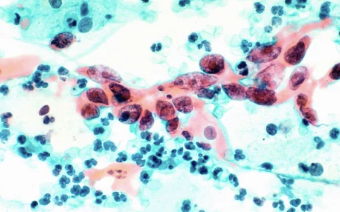

| 자궁경부세포검사(파파니콜로 검사) | 20세 이상 성경험 여성 | 2년마다 무료 국가검진 | 자궁경부암 조기 진단에 매우 효과적 |